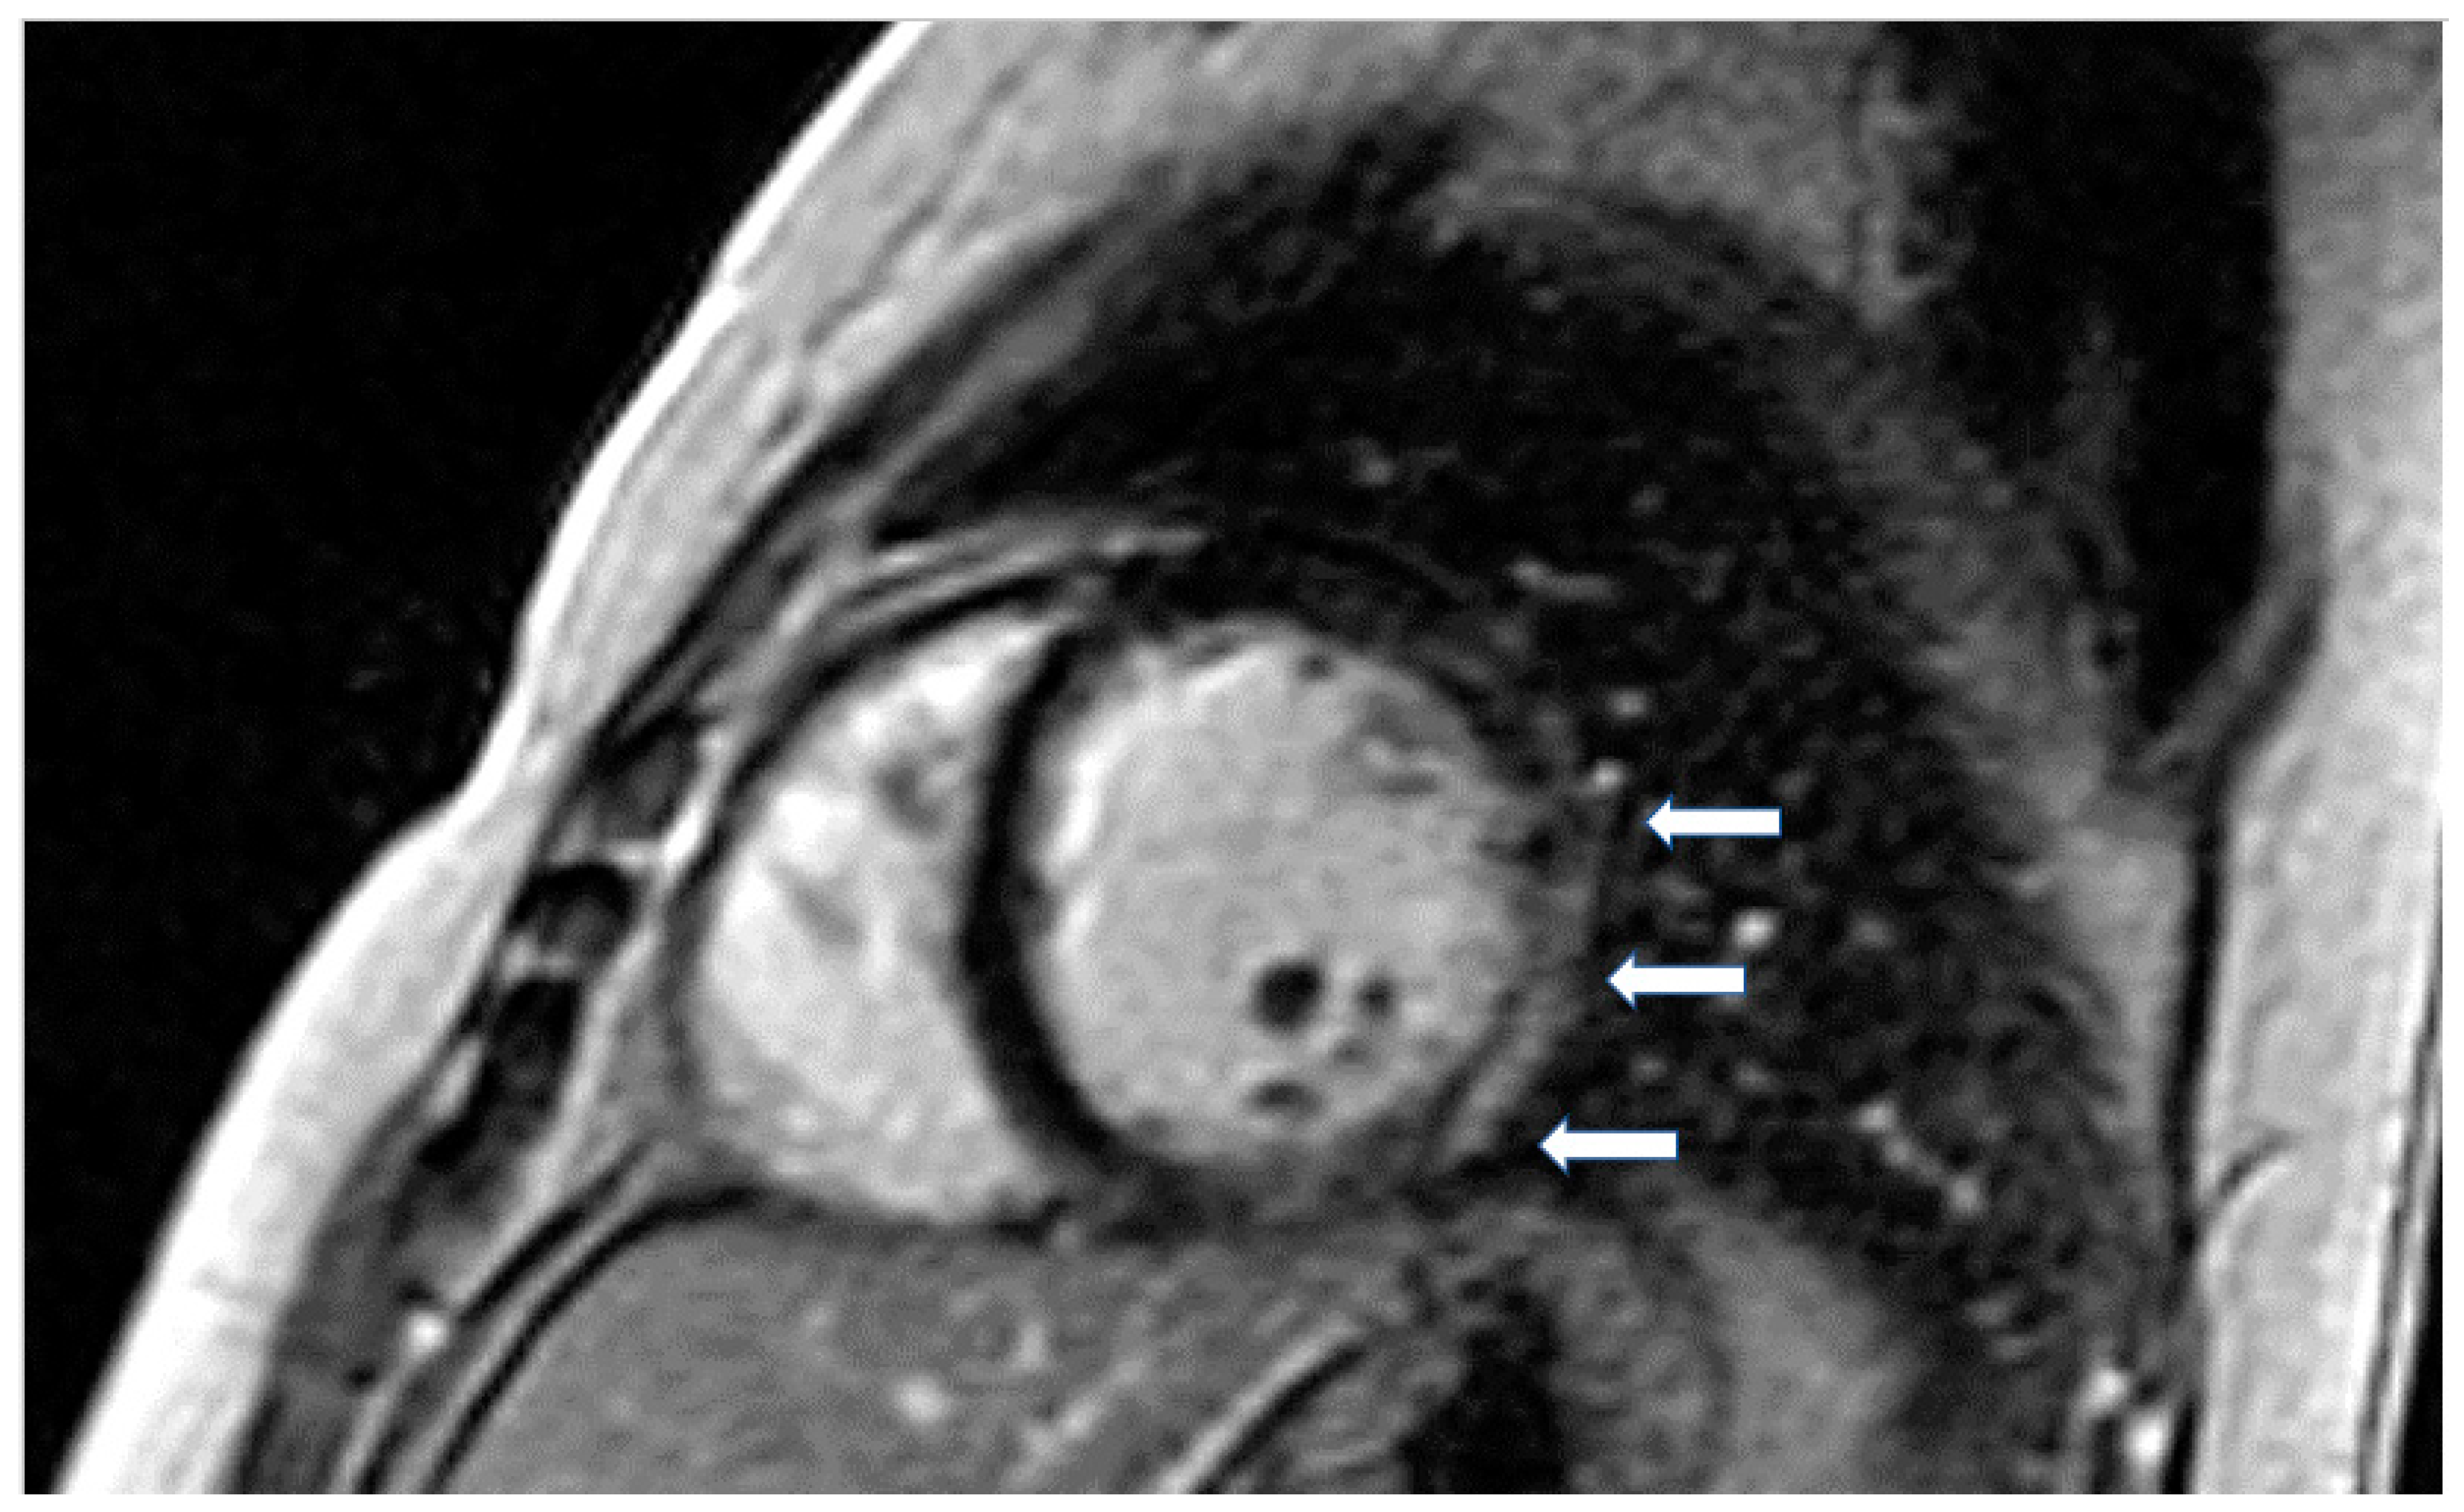

- T1-weighted images (T1-W) and late gadolinium enhancement (LGE): T1-W imaging provides information for a morphological assessment of the heart. Late gadolinium-enhanced T1-W images (LGE), taken 10–15 min after gadolinium-based contrast administrations using inversion recovery pulse sequences, allows for the detection of myocardial replacement fibrosis (scar) (Figure 1) [13]. LGE may also detect marked extracellular interstitial expansion in association with amyloidosis (amyloid deposition and fibrosis) and in pulmonary hypertension (myocardial disarray with increased collagen content without focal replacement fibrosis). In myocarditis, LGE mainly reflects inflammation, combined with or without fibrosis [13]. In the acute phase of myocarditis, LGE correlates with necrosis (associated with edema as assessed by T2 mapping), while in the chronic phase, it corresponds to fibrosis (with less or no edema) [13]. Thrombi (if not organized) do not accumulate contrast agents, making LGE ideal in excluding recent thrombi [14].Myocardial infarction is characterized by subendocardial or transmural LGE in the distribution of epicardial coronary arteries. Subepicardial or patchy LGE usually in the inferolateral wall is characteristic of myocarditis. Finally, diffuse subendocardial LGE that does not follow the typical distribution of epicardial coronary arteries is often associated with microvascular coronary artery disease, vasculitis, antiphospholipid syndrome, and endocrine disorders, such as Cushing syndrome and autoimmune thyroid disease [13].